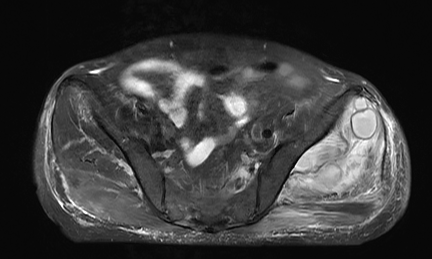

2023年1月3日,患者仍有下肢疼痛不适、尿量减少和水肿症状,实验室检查显示炎症指标进一步升高。双侧髋关节MRI平扫显示左侧髋关节周围软组织异常,提示可能存在感染。如图1:

▲图1:双侧髋关节MRI平扫